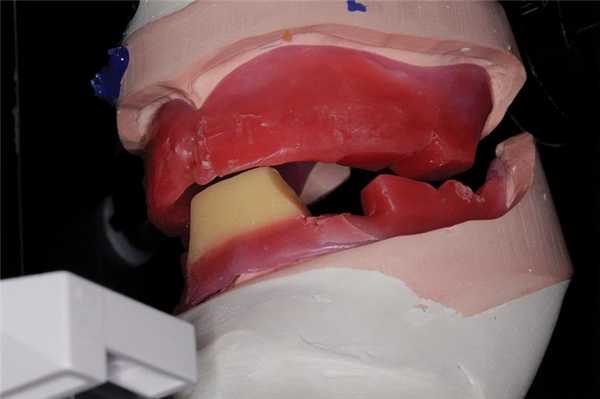

После определения надлежащего положения режущего края зубов верхней челюсти необходимо зарегистрировать позицию режущего края зубов нижней челюсти. Для этого используют пластинку базисного воска и восковый валик (фото 3). Высота воскового валика в переднем участке нижней челюсти должна составлять 18 мм от уровня преддверья до прогнозированного положения режущего края резцов. Для того, чтобы исключить ограничения при артикуляции нижней челюсти, дистальные части воскового валика делают ниже окклюзионной плоскости, после чего на валике формируют надрезы для соединения с восковым валиком верхней челюсти. По сути, применение специального воска в проекции передних зубов нижней челюсти является начальной точкой следующего этапа - определения вертикальной составляющей прикуса.

Фото 3. Использование специальной порции желтого воска для проверки фонетической функции с высотой равной 18 мм от преддверья полости рта.

После регистрации надлежащего положения передних зубов верхней челюсти восковой валик фиксируется на нижнюю челюсть, и врач просит пациента сосчитать до 60 или 70. Клиницист наблюдает за движениями нижней челюсти и корректирует нижний восковый валик до тех пор, пока пациент не сможет четко произнести звук «С». Если во время произношения звука «С», восковый валик нижней челюсти ударяется по передний зубам на верхней челюсти, то его можно несколько срезать. Также можно модифицировать конфигурацию валика в язычно-вестибулярном направлении (фото 4).

Фото 4. Вид в профиль: передние зубы установлены в верхнем восковом валике, а на нижнем валике установлена порция воска для проверки фонетической функции.